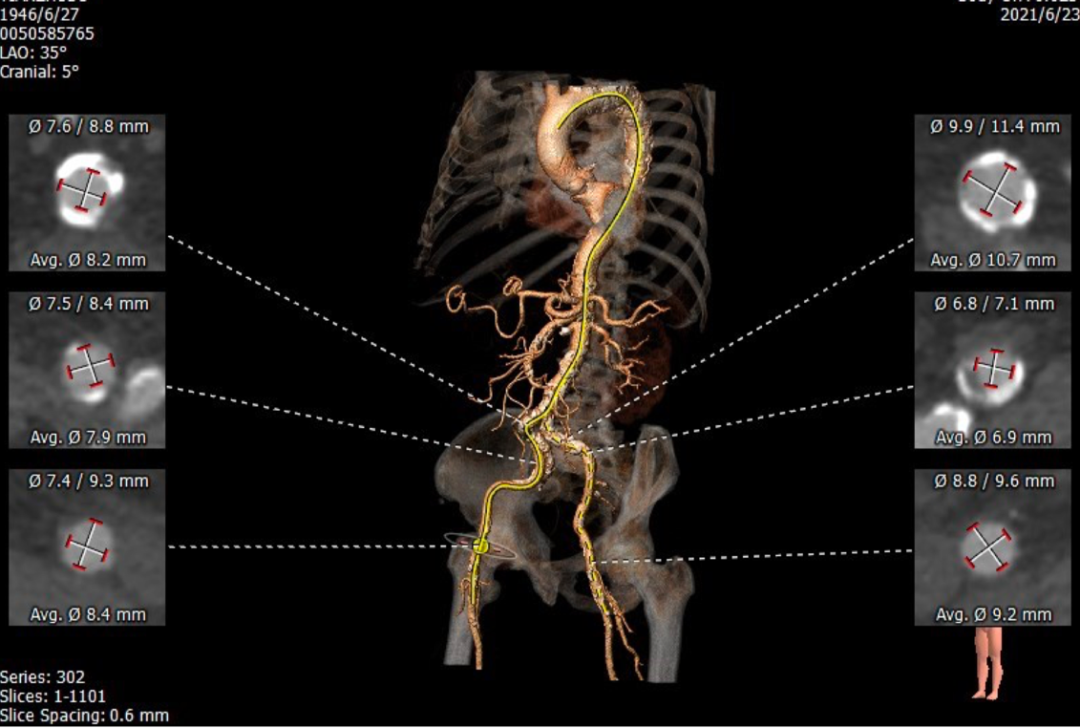

术前CT

CT提示为该患者三叶瓣,右无轻度融合,冠脉开口高度尚可,窦部空间可,髂总动脉近环形钙化,内径可,计划予以23mm球囊扩张,植入Venus A 26瓣膜。